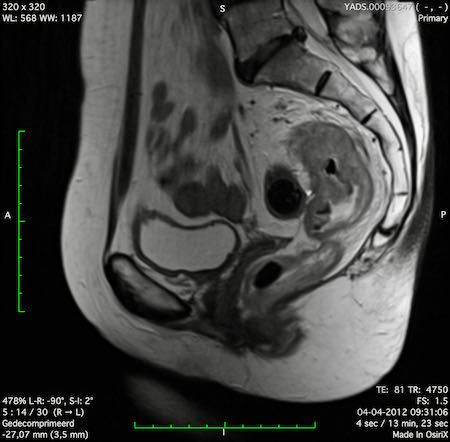

Hình ảnh

Các hình ảnh được cung cấp cho thấy ung thư biểu mô tế bào nhẫn với tình trạng dày lan tỏa thành trực tràng, hình ảnh bia bắn điển hình, và sự xâm lấn mỡ mạc treo trực tràng.